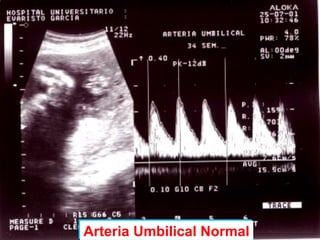

DOPPLER COLOR

- Detecta presencia y

dirección del flujo en un

vaso

- Diferencia flujo laminar o

turbulento

- Valora grado de resistencia

que el flujo tiene que vencer

Arteria Umbilical NormalArteria Umbilical Normal

 La onda pulsátil resultante es bifásica, con un pico (sístole) y un

valle (diástole). La sístole tiene un componente acelerativo y

uno desacelerativo..

 La relación S/D (sístole/diástole) es un parámetro de la

resistencia que debe vencer el flujo.

 Una gran resistencia se asocia con alta pulsatilidad y valores

reducidos de la velocidad del flujo diastólico.

 Una onda fisiológica presenta una imagen con la sístole y sus

dos componentes, el acelerativo y el desacelerativo y la

diástole.

 El componente acelerativo está en relación con la fuerza

contráctil del corazón y el desacelerativo con la complacencia de

la pared del vaso y la distancia al corazón.

 Mediante esta técnica se miden los índices de resistencia.

 El componente diastólico es la representación de la resistencia

periférica.